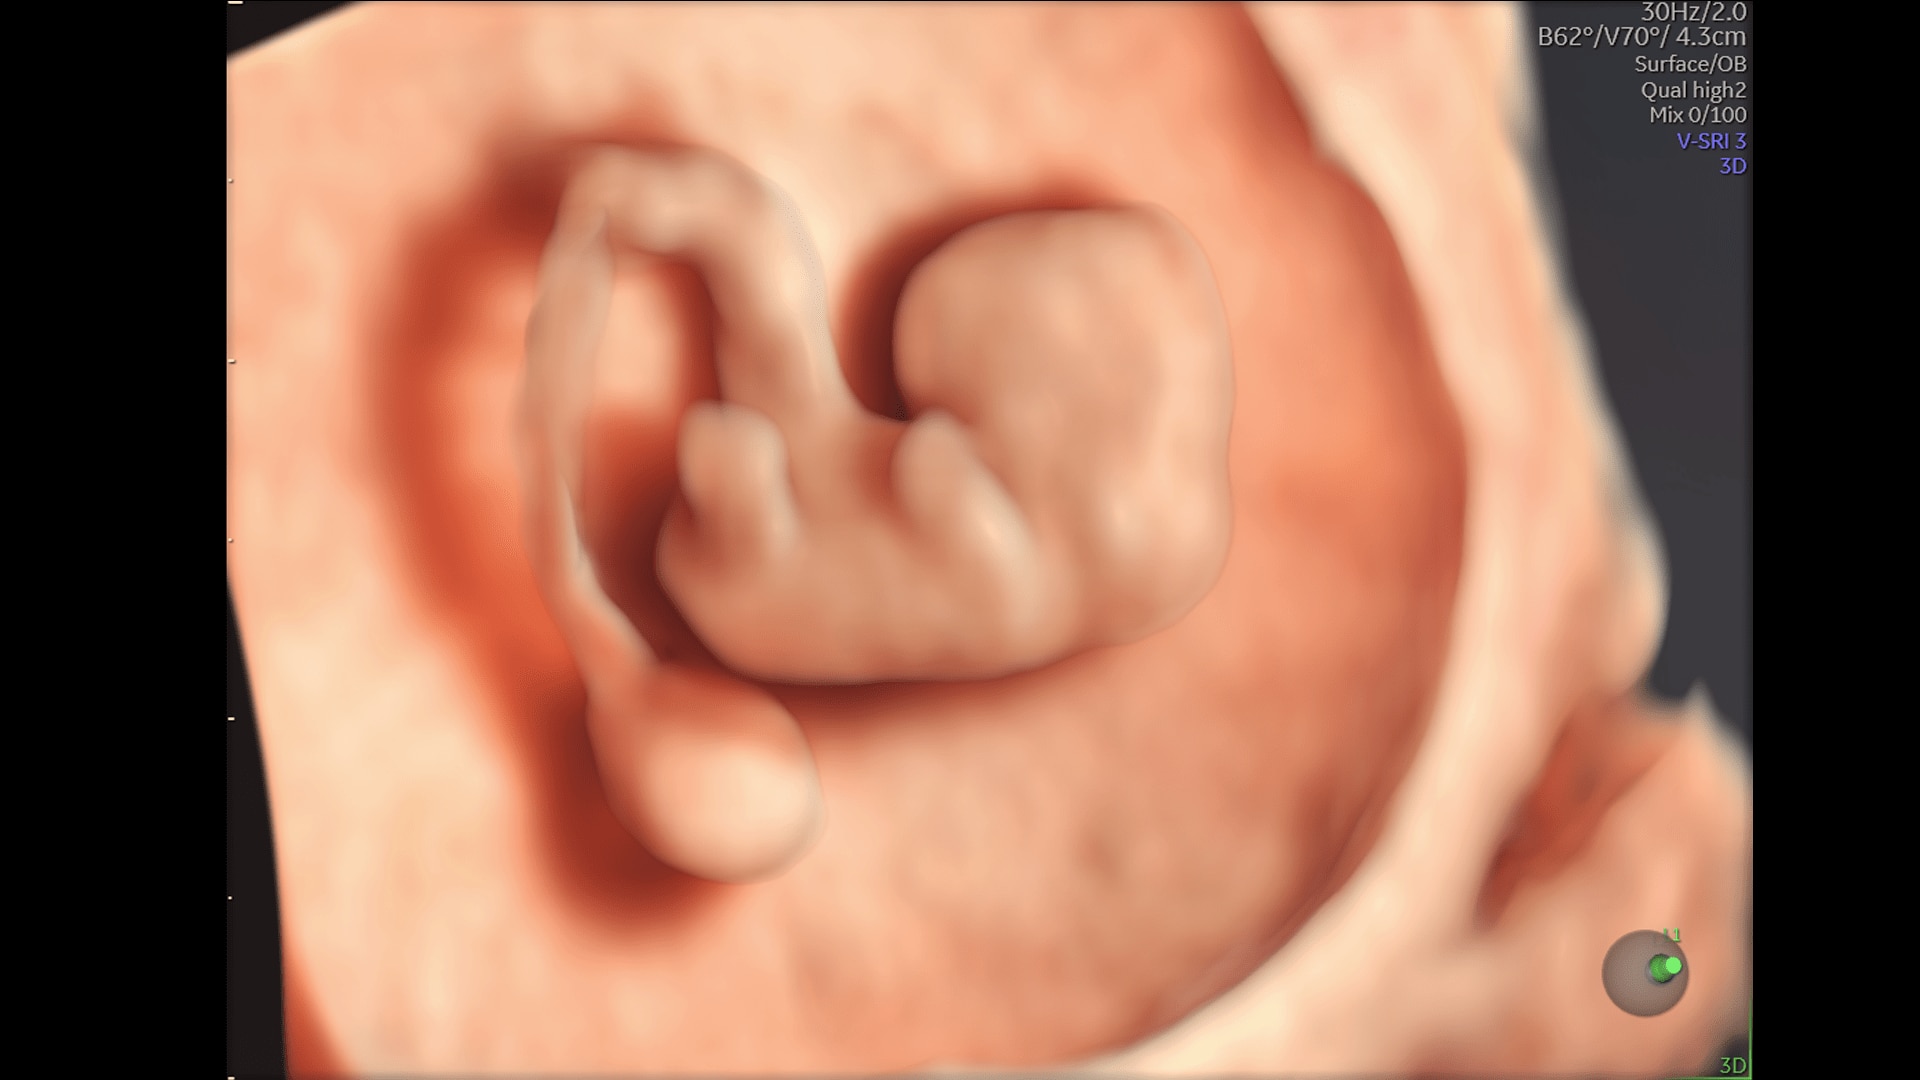

Enhanced Volume Imaging

Deliver next generation 3D/4D & Color images with HDlive Studio+

2D Imaging

The Ultimate Foundation

UltraHD

Super Fine Details

Obtain highly detailed images of the fetal brain, first trimester development, and other complex anatomy with increased axial and lateral resolution.